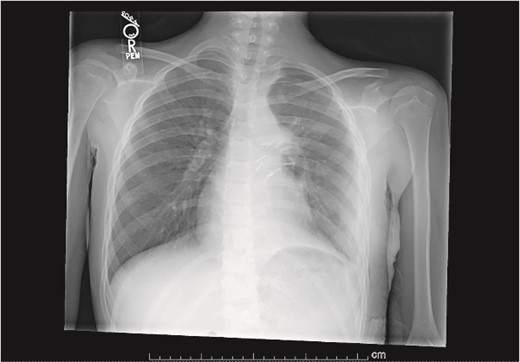

Our patient is a 10-year-old Caucasian female with a history of early adrenarche, ADHD, and COVID-19 and no past surgical history. She presented to the ED with a month-long history of persistent coughing, shortness of breath on exertion and speaking, and left-sided chest pain that began after a diagnosis of mildly symptomatic COVID-19. A physical exam revealed decreased breath sounds on the left, with a left-sided chest protrusion. A plain film and CT demonstrated a normal right lung, with a significant mediastinal shift toward the right, displacement of the heart into the right hemithorax, with complete whiteout of the left hemithorax, and demonstrating a mix of solid and cystic foci, with a round opacification at the left lung base (Figs 1 and 2). The patient underwent an uncomplicated left thoracotomy with excision of two masses, one being 22.5 × 21.0 × 10.5 cm and the other being 13.5 × 11.5 × 6.2 cm. These masses weighed 2394 g in aggregate. The specimens consisted of well-encapsulated tumors attached to the posterior aspect of the chest wall. A regional, positive lymph node measuring 3.0 × 2.2 × 1.0 cm was also resected. Due to the large size of the tumor and the requirement for clean margins, parts of the latissimus dorsi and serratus anterior muscles were also resected. By postoperative day (POD) 0, the left lung had already filled the left hemithorax, and the mediastinal shift had corrected (Fig. 3). The chest tube was removed on POD 5, and a plain film showed continued expansion of the lung to full size and resolving pulmonary edema and atelectasis (Fig. 4). The patient was discharged home on POD 5. The tumor staging was T4N1M0. The tumor was positive for vimentin, CD56, synaptophysin, chromogranin, and NSE. The tumor was negative for pancytokeratin, Cam5.2, EMA, S100, desmin, SMA, SOX10, HMB45, CD117, DOG1, CD99, PR, CD68, WT1, CD30, p53, Alk1, GFAP, and nuclear β-catenin. Next-generation sequencing showed an MGA:NUTM1 fusion, supporting a final diagnosis of high-grade MGA:NUTM1 fusion SCS. Given the size and grading of the tumor, the patient underwent adjuvant CT-RT with ifosfamide, doxorubicin, and proton beam radiotherapy, with supportive doses of MESNA and dexrazoxane for 4.5 months post-operatively. The basis of this treatment is ARST0332 Arm C [6]. Before treatment initiation, the patient underwent an uncomplicated left oophorectomy for reproductive cryopreservation. A PET/CT prior to CT-RT showed hypermetabolic activity in several areas. These included the pleural resection margin, a mediastinal lymph node concerning for metastasis versus postsurgical change, and a left axillary lymph node concerning for metastatic disease. During treatment, the patient contracted human metapneumovirus and rhino/enterovirus, resulting in febrile neutropenia. The patient was successfully treated with blood and platelet transfusions and pegfilgrastim. Upon completion of CT-RT, PET/CT imaging showed no evidence of residual disease, with minimal focal hypermetabolic activity as compared to the previous imaging (Fig. 5).

Plain film on postoperative day 0 depicting the recovery of the left lung post-surgical resection.

Plain film postoperative day 5, after removal of chest tube, showing improving pulmonary status in the left hemithorax.